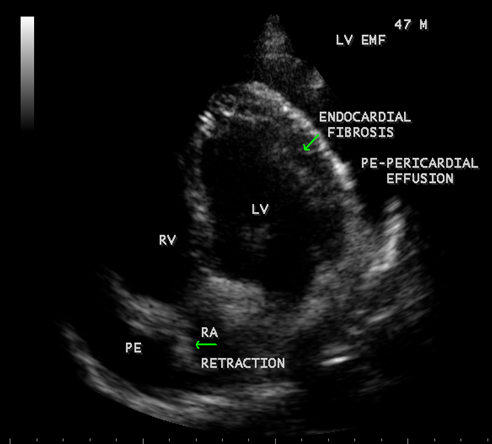

Figure 41: showing Endomyocardial fibrosis with moderate pericardial effusion and right atrial notch (RA retraction) in a year 47-year old male

When the endocardium is replaced by collagenous fibrosis (consist of collagen deposition and fibroblast proliferation), the final fibrotic stage is reached after several years of disease activity. Fibrotic obliteration of the apices of the affected ventricles is the hallmark of the disorder and fibrosis involving the papillary muscles and chordae tendineae leading to atrioventricular valve distortion and regurgitation. In the left ventricle, the fibrosis extends from the apex to the posterior mitral leaflet, usually sparing the anterior mitral leaflet and outflow tract and cause PML (posterior mitral leaflet) distortion and regurgitation. Like the peculiar geographical distribution, the fibrotic endomyocardial involvement stops short of the ventricular outflow tract like a ridge [17] as shown in Figures 15,29,31,35 and 44. The fibrotic tissue often creates a nidus for thrombus formation, which can be extensive. Atrial thrombi also occur and the right atrium may be aneurysmally dilated. Aneurysmal right atrium with spontaneous echo contrast was detected in a 32- year old male as shown in Figure 36 [18- Figure 3]. In addition, there are fibrosis and granular septation extending into the underlying myocardial tissue and myocyte hypertrophy is common [19]. Fibrotic process causes tethering of leaflets into ventricular walls and may mimic Ebstein’s malformation as shown in Figure 38[20],[21]. Fibrosis increases the stiffness of the heart, resulting restrictive physiology, AV (atrioventricular) valve regurgitation which has been linked to atrial arrhythmias such as atrial fibrillation as shown in Figures 19 and 20 in a 62-year old female. Atrial fibrillation has been reported in more than 30% of patients with EMF. Fibrosis impairs activation patterns of the conduction system and may provide substrate for wave breaks and reentry [22]. Fibrosis reduces conduction velocity and cause conduction abnormalities like junctional rhythms, heart blocks as shown in Figure 21 and 22 in a 75-year old female and atrioventricular conduction delay [23].

A large pericardial effusion is often present and noted as another peculiar feature of this disease [27]. Pericardial effusion and ascites dominate the clinical picture of right ventricular EMF [28], [29], [30]. Etiology of pericardial effusion is possibly inflammatory and EMF is to be considered as ‘pancarditis’ since all the layers are involved. Adhesions between the parietal and visceral layers of the pericardial sac may develop and visible as strong fibrotic strands as shown in Figures 29. A right ventricular EMF presented with massive pericardial effusion was detected in a 85 –year old female as shown in Figure 16, 17 and 29[31]. Cardiomegaly can be exaggerated by pericardial effusion, and pleural effusion is also a common finding as shown in Figure 9 [16-Figure 2]. Giant ascites in EMF is not fully explained by congestion alone and it is due to peritoneal inflammation and reduced reabsorption of peritoneal fluid, caused by fibrosis since the fluid is an exudate with predominant lymphocytes. The triad of elevated JVP (Jugular venous pressure), ascites and hepatomegaly formed the hallmark of right ventricular EMF.

Today echocardiography is used as the screening tool at the community level as the diagnosis of EMF could be confirmed at the bedside. Echocardiography accurately assesses the pathological abnormalities of chronic disease and it is the gold standard technique for the diagnosis of EMF [36]. It reveals dense endomyocardial echocardiograms along different parts of the mural and valvular endocardium and AV valve dysfunction [37] as shown in Figures 3 to 44. The typical feature of EMF is the obliteration of trabecular portion of the ventricle and in advanced cases, there is shrinkage of the cavities creating an apical notch, regurgitation, slow flow with spontaneous echo contrast as in Figure 36 and considerable pericardial effusion. Similar to apical notch of right ventricle, a right atrial notch is well seen as contraction (or retraction) of tricuspid annulus as in Figure 40 and right atrial notch as in Figure 41 and 42, indicating the retraction of rightatrial cavity as a peculiar feature of right ventricular EMF. Biventricular enlargement as shown in Figure 40 and biatrial enlargement as in Figure 32 are the characteristic features of advanced stage of EMF. The fibrosed muscular trabeculae extending into the cavities from the walls of the chambers in the right ventricle visible as ‘cobra heads’ as in Figure 4 and in pericardial sac as in Figure 29, in the left ventricle. Aneurysmal right ventricle with scattered areas of fibrosis in the sub tricuspid region and a notch in the right atrium is well seen in a 14 –year old boy as in Figure 42 . Right atrial notch is frequently noticed in EMF patients as shown in Figure 41 in a 47- year old male with left ventricular EMF and moderate pericardial effusion.